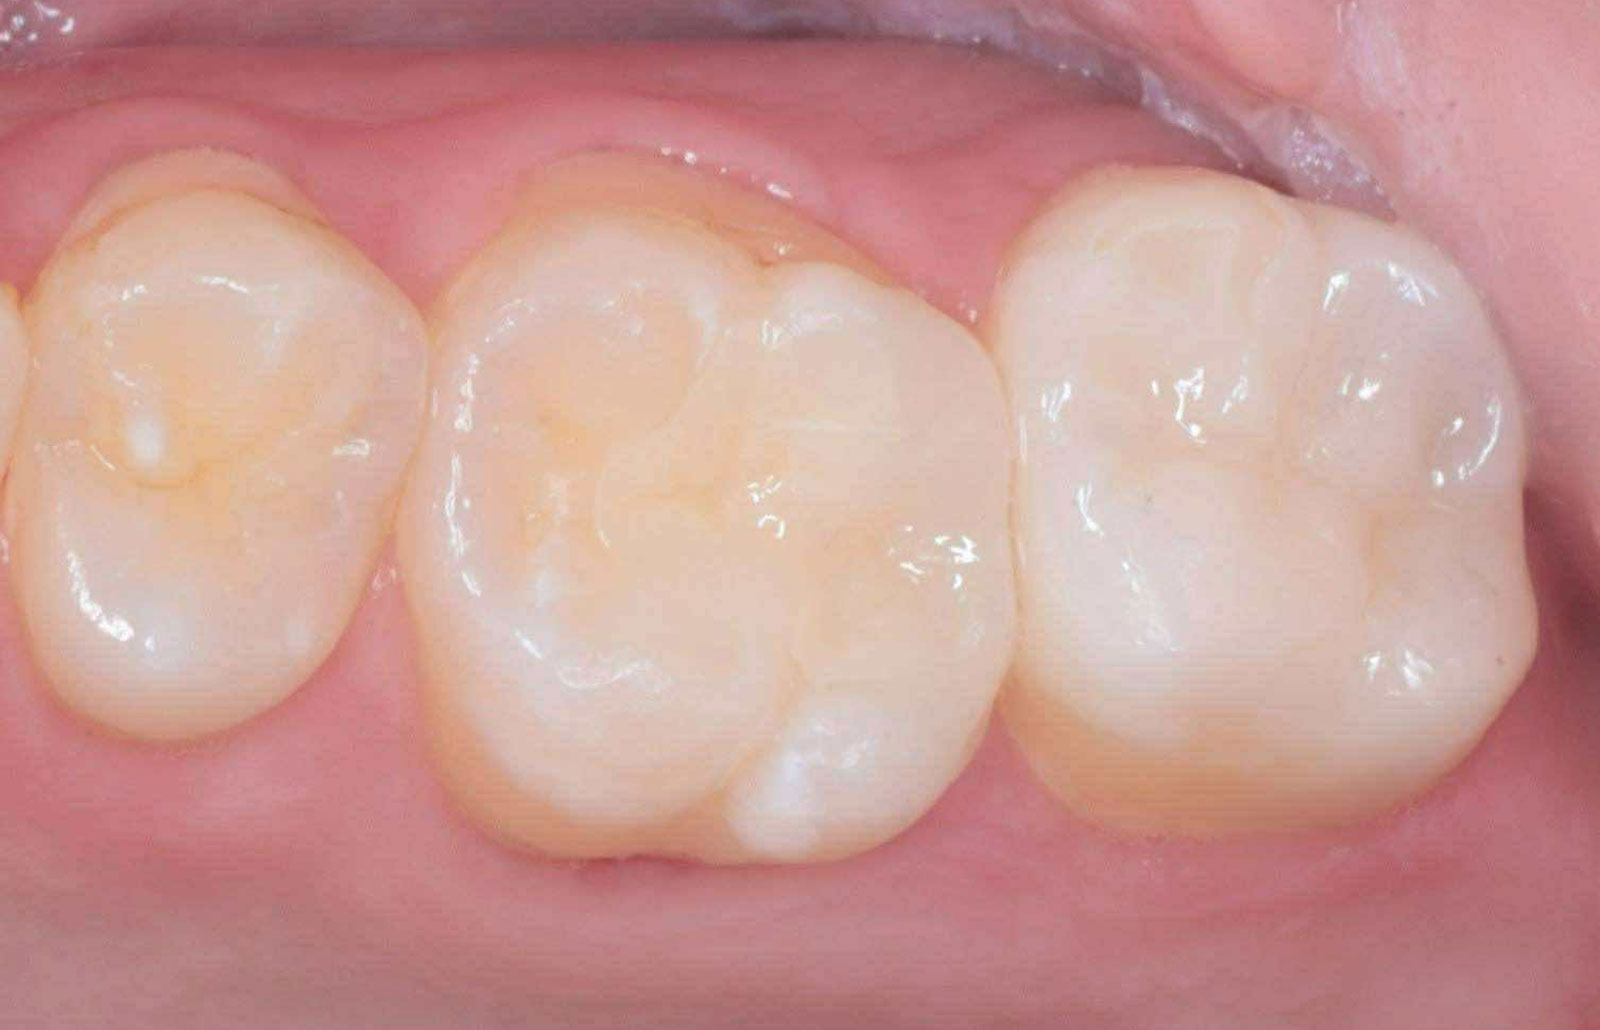

当院では、これらを組み合わせた「セラミック矯正」を提供しています。具体的には、セラミックの被せ物を使って歯の形や色を整えながら、同時に歯並びも改善していきます。

セラミック矯正 ![]() | 1回~3回 | セラミックの被せ物 | ・抜歯は不要 |

比較表から分かるように、セラミック矯正は短期間で美しい歯になるというメリットがあります。

しかし、その一方で「健康な歯を削る」必要があります。セラミックの被せ物を装着するためには、どうしても天然歯を削らなければなりません。